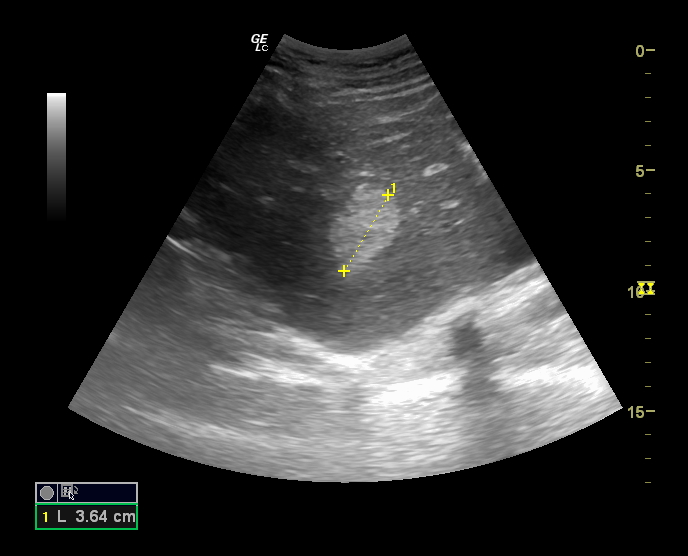

Hallazgos ecográficos

En la última ecografía realizada en febrero de 2023 presenta múltiples hemangiomas (lesiones hiperecogénicas), el de mayor tamaño en lóbulo caudado de 41 x 38 mm, segmento VIII dos, uno de 53 x 40 mm y otro de 17 mm, en segmento IV de 16 mm y en segmento VII de 9 mm.